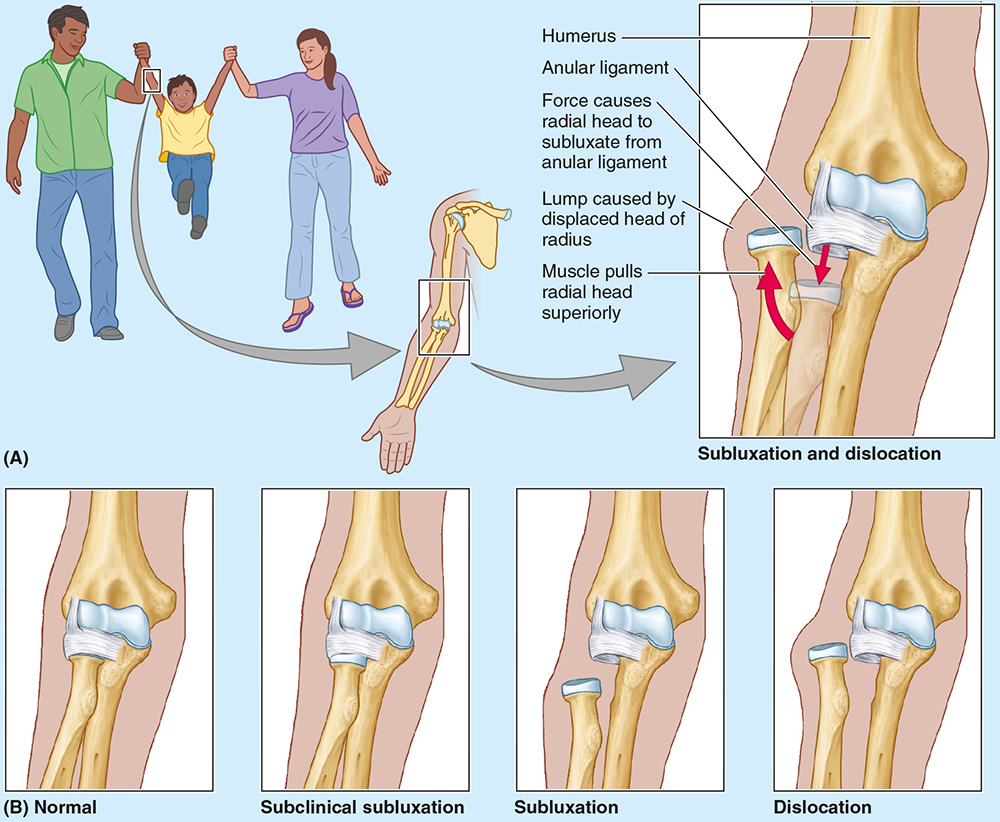

Nursemaid’s elbow is a common injury in preschool children, especially girls, caused by sudden pulling of the pronated forearm (e.g., lifting a child). The _________ tear causes subluxation of the radial head.

annular ligament

Nursemaid’s elbow is a common injury in preschool children, especially girls, caused by sudden pulling of the pronated forearm (e.g., lifting a child). The annular ligament tear causes __________ of the radial head.

subluxation

Treatment of nursemaid’s elbow involves?

Treatment involves supination with elbow flexion; healing occurs with sling use for 2 weeks.

The elbow is stabilized by the ulnar and radial collateral ligaments, whereas the _____________ holds the radius against the ulna for rotation.